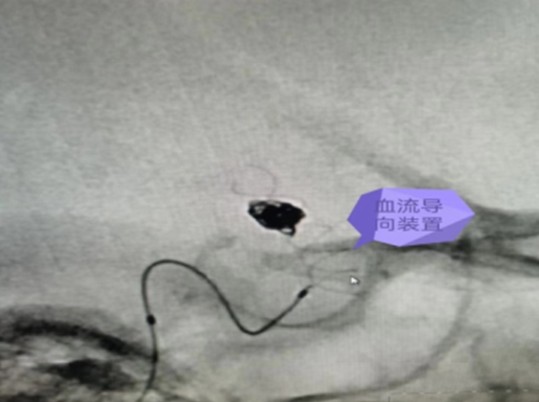

7月14日,在麻醉科及介入手術(shù)室的密切配合下,神經(jīng)外科醫(yī)師團(tuán)隊(duì)順利完成了此例后交通段血泡樣動(dòng)脈瘤血流導(dǎo)向裝置+彈簧圈栓塞手術(shù),拆除了龍女士腦子里的“不定時(shí)炸彈”。

據(jù)悉,顱內(nèi)血流裝置(PED)是一種治療顱內(nèi)復(fù)雜動(dòng)脈瘤新型的治療方式,通過置入所到病變動(dòng)脈后,使動(dòng)脈內(nèi)的血流動(dòng)力學(xué)發(fā)生改變,緩慢的在動(dòng)脈瘤內(nèi)形成血栓,內(nèi)膜上皮攀爬到支架表面從而來修復(fù)病變血管使其發(fā)生血管重建來修復(fù)病變的載瘤動(dòng)脈。血流導(dǎo)向裝置的發(fā)展更新了動(dòng)脈瘤的治療理念,對顱內(nèi)復(fù)雜動(dòng)脈瘤的治療結(jié)果產(chǎn)生革命性的變化,具有手術(shù)微創(chuàng),操作簡單,安全性相對較高,在降低動(dòng)脈瘤復(fù)發(fā)方面更具有優(yōu)勢。